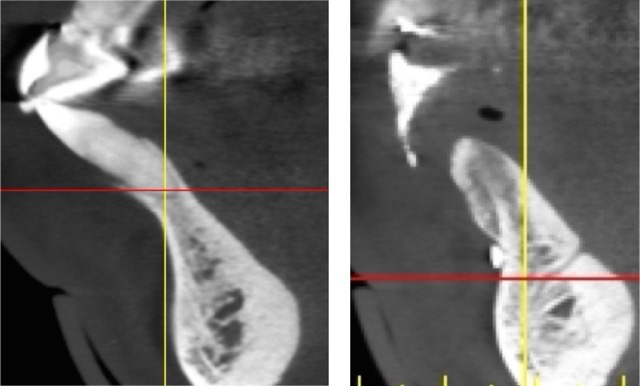

Fig 5. Sagittal cross-sections of CBCT images depicting Grade I (Left), Grade II (Center), and Grade III (Right) sockets. Note the level of the buccal plate relative to the cementoenamel junction that is elucidated by this cross-cut.

Fig 2. (Left) An example of a mandibular anterior tooth, No. 27, that was treated with extraction and replacement with a single implant. Note the concavity in the alveolus apical to the tooth. There was inadequate apical bone for extraction and immediate implant placement, thus a 2-stage surgical approach was planned. In this case, had only the socket been filled with grafting material there still would not have been enough bone present for proper implant placement. A full-thickness flap was created and GBR performed to both preserve the site and correct the apical deficiency for implant placement. (Right) Note the new bone formed buccal to the ridge and the bone now available for implant placement.

Figure 2